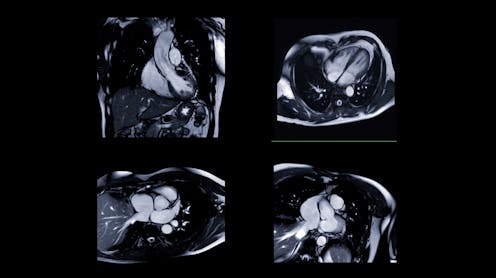

AI systems are already transforming healthcare. They can analyse chest X-rays, read heart scans and flag potential issues faster than human doctors – in some cases, in seconds rather than minutes. Hospitals are adopting these tools to improve efficiency, reduce costs and standardise care.

In the heart scan study, researchers found that the AI model wasn’t actually focusing on the heart itself, where there were few visible differences linked to racial categories. Instead, it drew information from areas outside the heart, such as subcutaneous fat as well as image artefacts – unwanted distortions like motion blur, noise, or compression that can degrade image quality. These artefacts often come from the scanner and can influence how the AI interprets the scan.

Build transparency: many AI systems are considered “black boxes” because we don’t understand how they reach their conclusions. The heart scan study used heat maps to show which parts of an image influenced the AI’s decision, creating a form of explainable AI that helps doctors and patients trust (or question) results – so we can catch when it’s using inappropriate shortcuts.